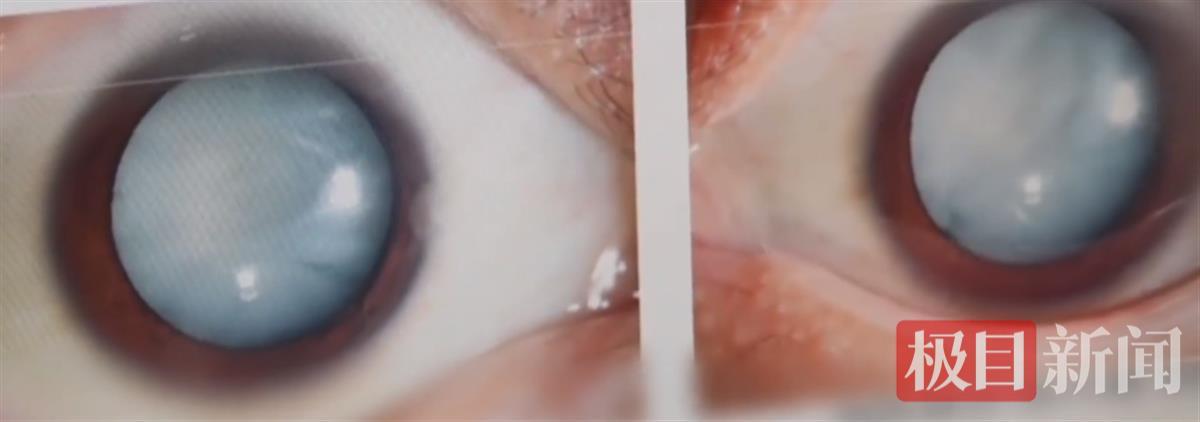

该院白内障与老视专科孙明副主任医师为小吴进行了详细检查,她发现,小吴的白内障情况极为严重,晶状体几乎完全浑浊,从外观上看,双眼毫无神采,瞳孔中央一片雪白。“双眼的晶状体几乎完全是浑浊的。即使在肉眼下,我们都看到他的双眼是无神的,瞳孔中央完全是白的。”孙明副主任医师表示。

通常情况下,白内障多见于老年群体,二十多岁的患者十分罕见。在排除外伤因素后,孙明副主任医师初步判断小吴患上的可能是代谢性白内障,而血糖检测结果更是令人咋舌——他的血糖数值超过30mmol/L,几乎是正常数值的三到四倍。“糖尿病之所以会引发白内障,是因为体内的一些代谢发生异常,造成了眼内晶状体的代谢也发生异常。”孙明副主任医师补充。